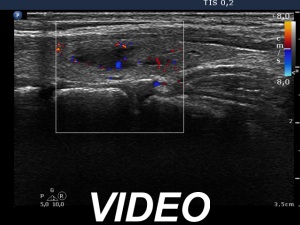

First examination (first row of images)

Clinical data: A 21-year-old woman was referred for evaluation on a nodular goiter. She has noticed an enlargement in the left lobe for a year. On evaluation in another institute, a cystic nodule was diagnosed with a 26 mm maximal diameter and 3 mL brown fluid was aspirated. Cytology resulted in benign cystic lesion.

Palpation: The right lobe was suspicious having a nodule.

Laboratory test: TSH 2.21 mIU/L.

Ultrasonography. The thyroid was echonormal and presented a moderately hypoechoic nodule in the right lobe and a cystic nodule with minimally hypoechoic solid part corresponding to the previously aspirated cystic lesion. The largest diameter of the latter was 11 mm which means that cyst has not refilled. The nodule in the right lobe showed irregular, more hypoechoic areas all along at the periphery. This pattern mimicked halo sign, but indeed the lesion did not have a real halo. The vascularization of the nodule in the right lobe presented an irregularly increased intranodular blood flow while the lesion in the left lobe did signs of perinodular vascularization.

Cytology was performed form the lesion in the right lobe and resulted in follicular proliferation.

Combined ultrasound-cytological diagnosis was benign follicular proliferation.

Suggestion: ultrasound in a year.